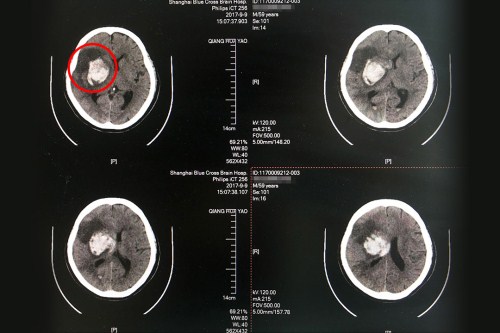

術(shù)前CT:右側(cè)基底節(jié)區(qū)大量出血,血腫破入腦室系統(tǒng),右側(cè)高顱壓。

術(shù)后CT:右側(cè)額顳枕葉梗塞伴右側(cè)基底節(jié)區(qū)出血吸收中,皮層血供再通,較前好轉(zhuǎn)